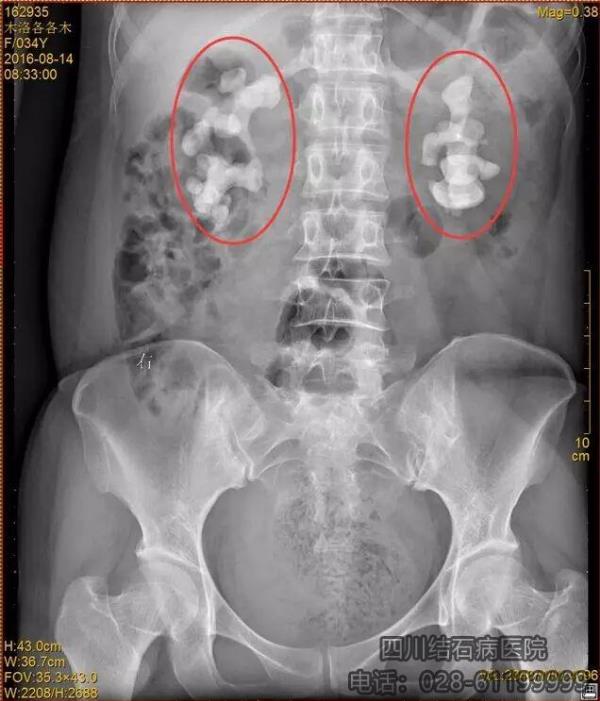

二是涼山州患者各各木,因飲生水30余年,加上常曬太陽(yáng)等原因,導(dǎo)致年僅34歲就患上雙腎巨大鑄型結(jié)石。我院醫(yī)生歷經(jīng)3個(gè)月,實(shí)施了4期經(jīng)皮腎鏡碎石取石術(shù),終將結(jié)石取凈。這兩起特殊病例引起新聞媒體以及國(guó)內(nèi)廣大人民的廣泛關(guān)注。

患者各各木體內(nèi)的巨大結(jié)石。